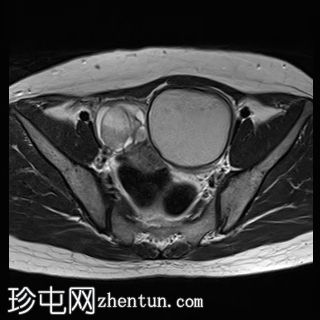

轴位

T1加权像

左侧卵巢可见一巨大、无强化囊性病变。该病变壁薄,在T1加权像和T1脂肪抑制像上呈均匀高信号,在T2加权像上呈独特的阴影状,符合子宫内膜异位囊肿的特征。值得注意的是,该病变可见两个增强灶,但未见内部实性成分或对比增强。

此外,右侧卵巢内数个小的、无强化囊性病变表现出类似的信号特征,这也符合子宫内膜异位囊肿的特征。

右侧卵巢内还有另一个囊性病变,在T1加权像上呈低信号,在T2加权像上呈高信号,并可见液平面。该病变无对比剂强化,可能代表出血性黄体囊肿。

双侧卵巢向内侧移位,形成“接吻卵巢征”。